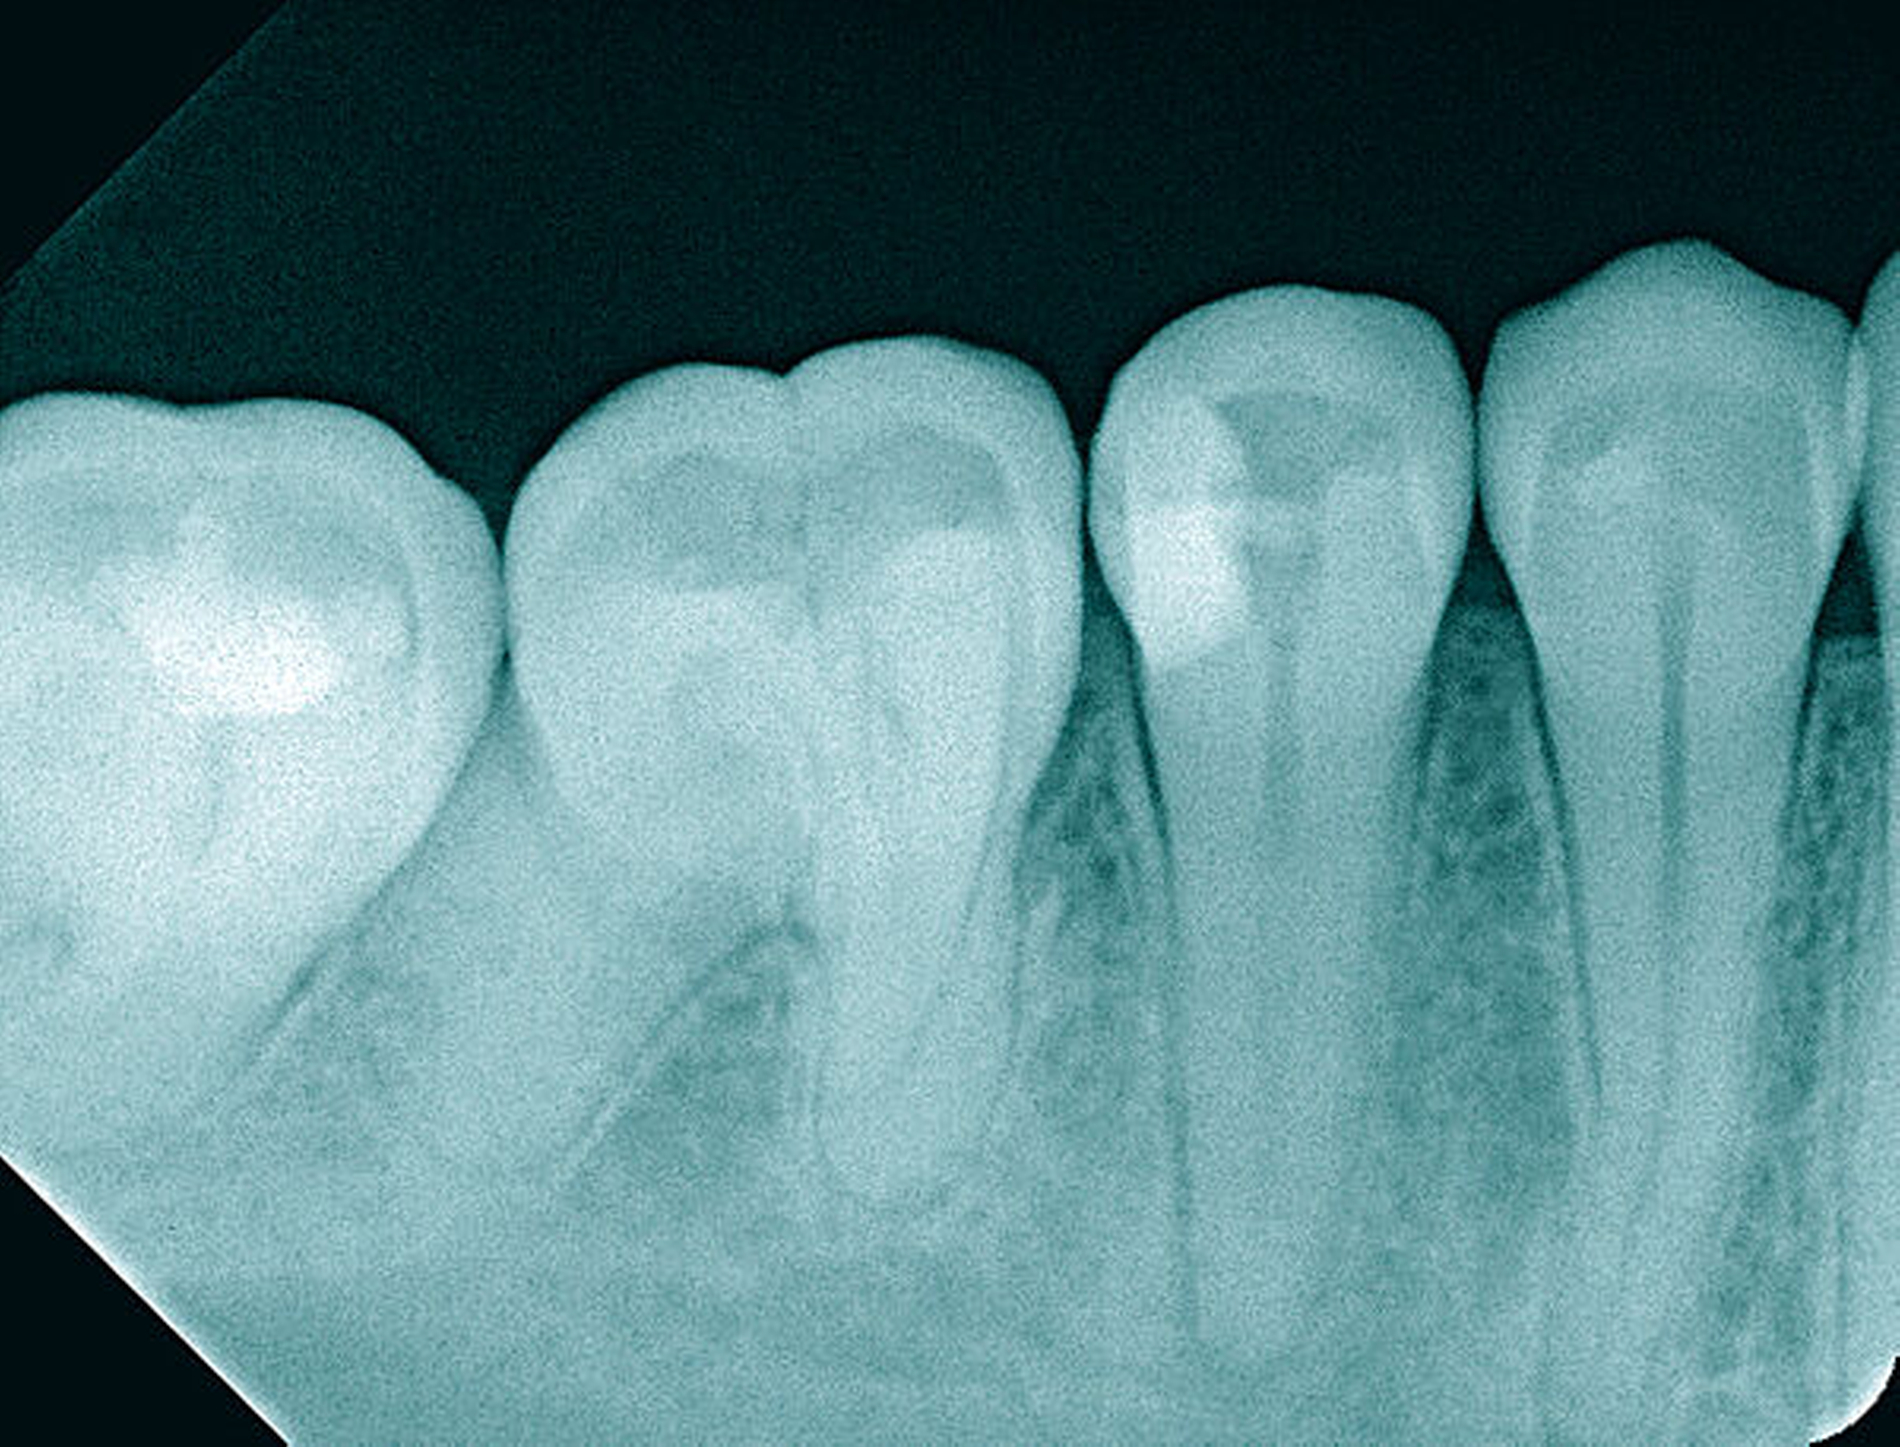

Die Schwierigkeit in der Therapie nimmt zu, wenn die Wurzelkanalkrümmung mehr als 30 Grad beträgt, der Krümmungsradius abnimmt (enge Krümmung) oder Mehrfachkrümmungen vorliegen [Duke et al., 2015; Pedulla et al., 2020]. Typisch für Mehrfachkrümmungen sind vor allem mesiale Wurzelkanäle unterer Molaren (Abbildung 4).

Sollte eine Konfluenz beider mesialer Wurzelkanäle am unteren Molaren vorliegen, kommt es zu einem abrupten Richtungswechsel und Instrumente können leichter frakturieren oder Stufen präparieren, so dass die Arbeitslänge nicht mehr erreicht werden kann.